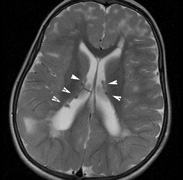

Intracranial leptomeningeal capillary vascular malformation (Figs. 21 and 22) is associated with seizures and contralateral neuromuscular weakness. Central nervous system involvement correlates highly with ipsilateral involvement of the V1 dermatome by a PWS.208,218

Fig. 22. Axial T2-weighted (a) and coronal T1-weighted (b) images of a 16-year-old boy with a port-wine lesion over the right side of his face. The right hemisphere is markedly atrophic and abnormal draining veins are seen within the right lateral ventricle (arrowheads). (c, d) The entire right hemisphere is covered by an enhancing pial angioma and the choroid plexi are enlarged. Enhancing retinal angiomas (arrows), typical of Sturge-Weber syndrome, are seen in (d).